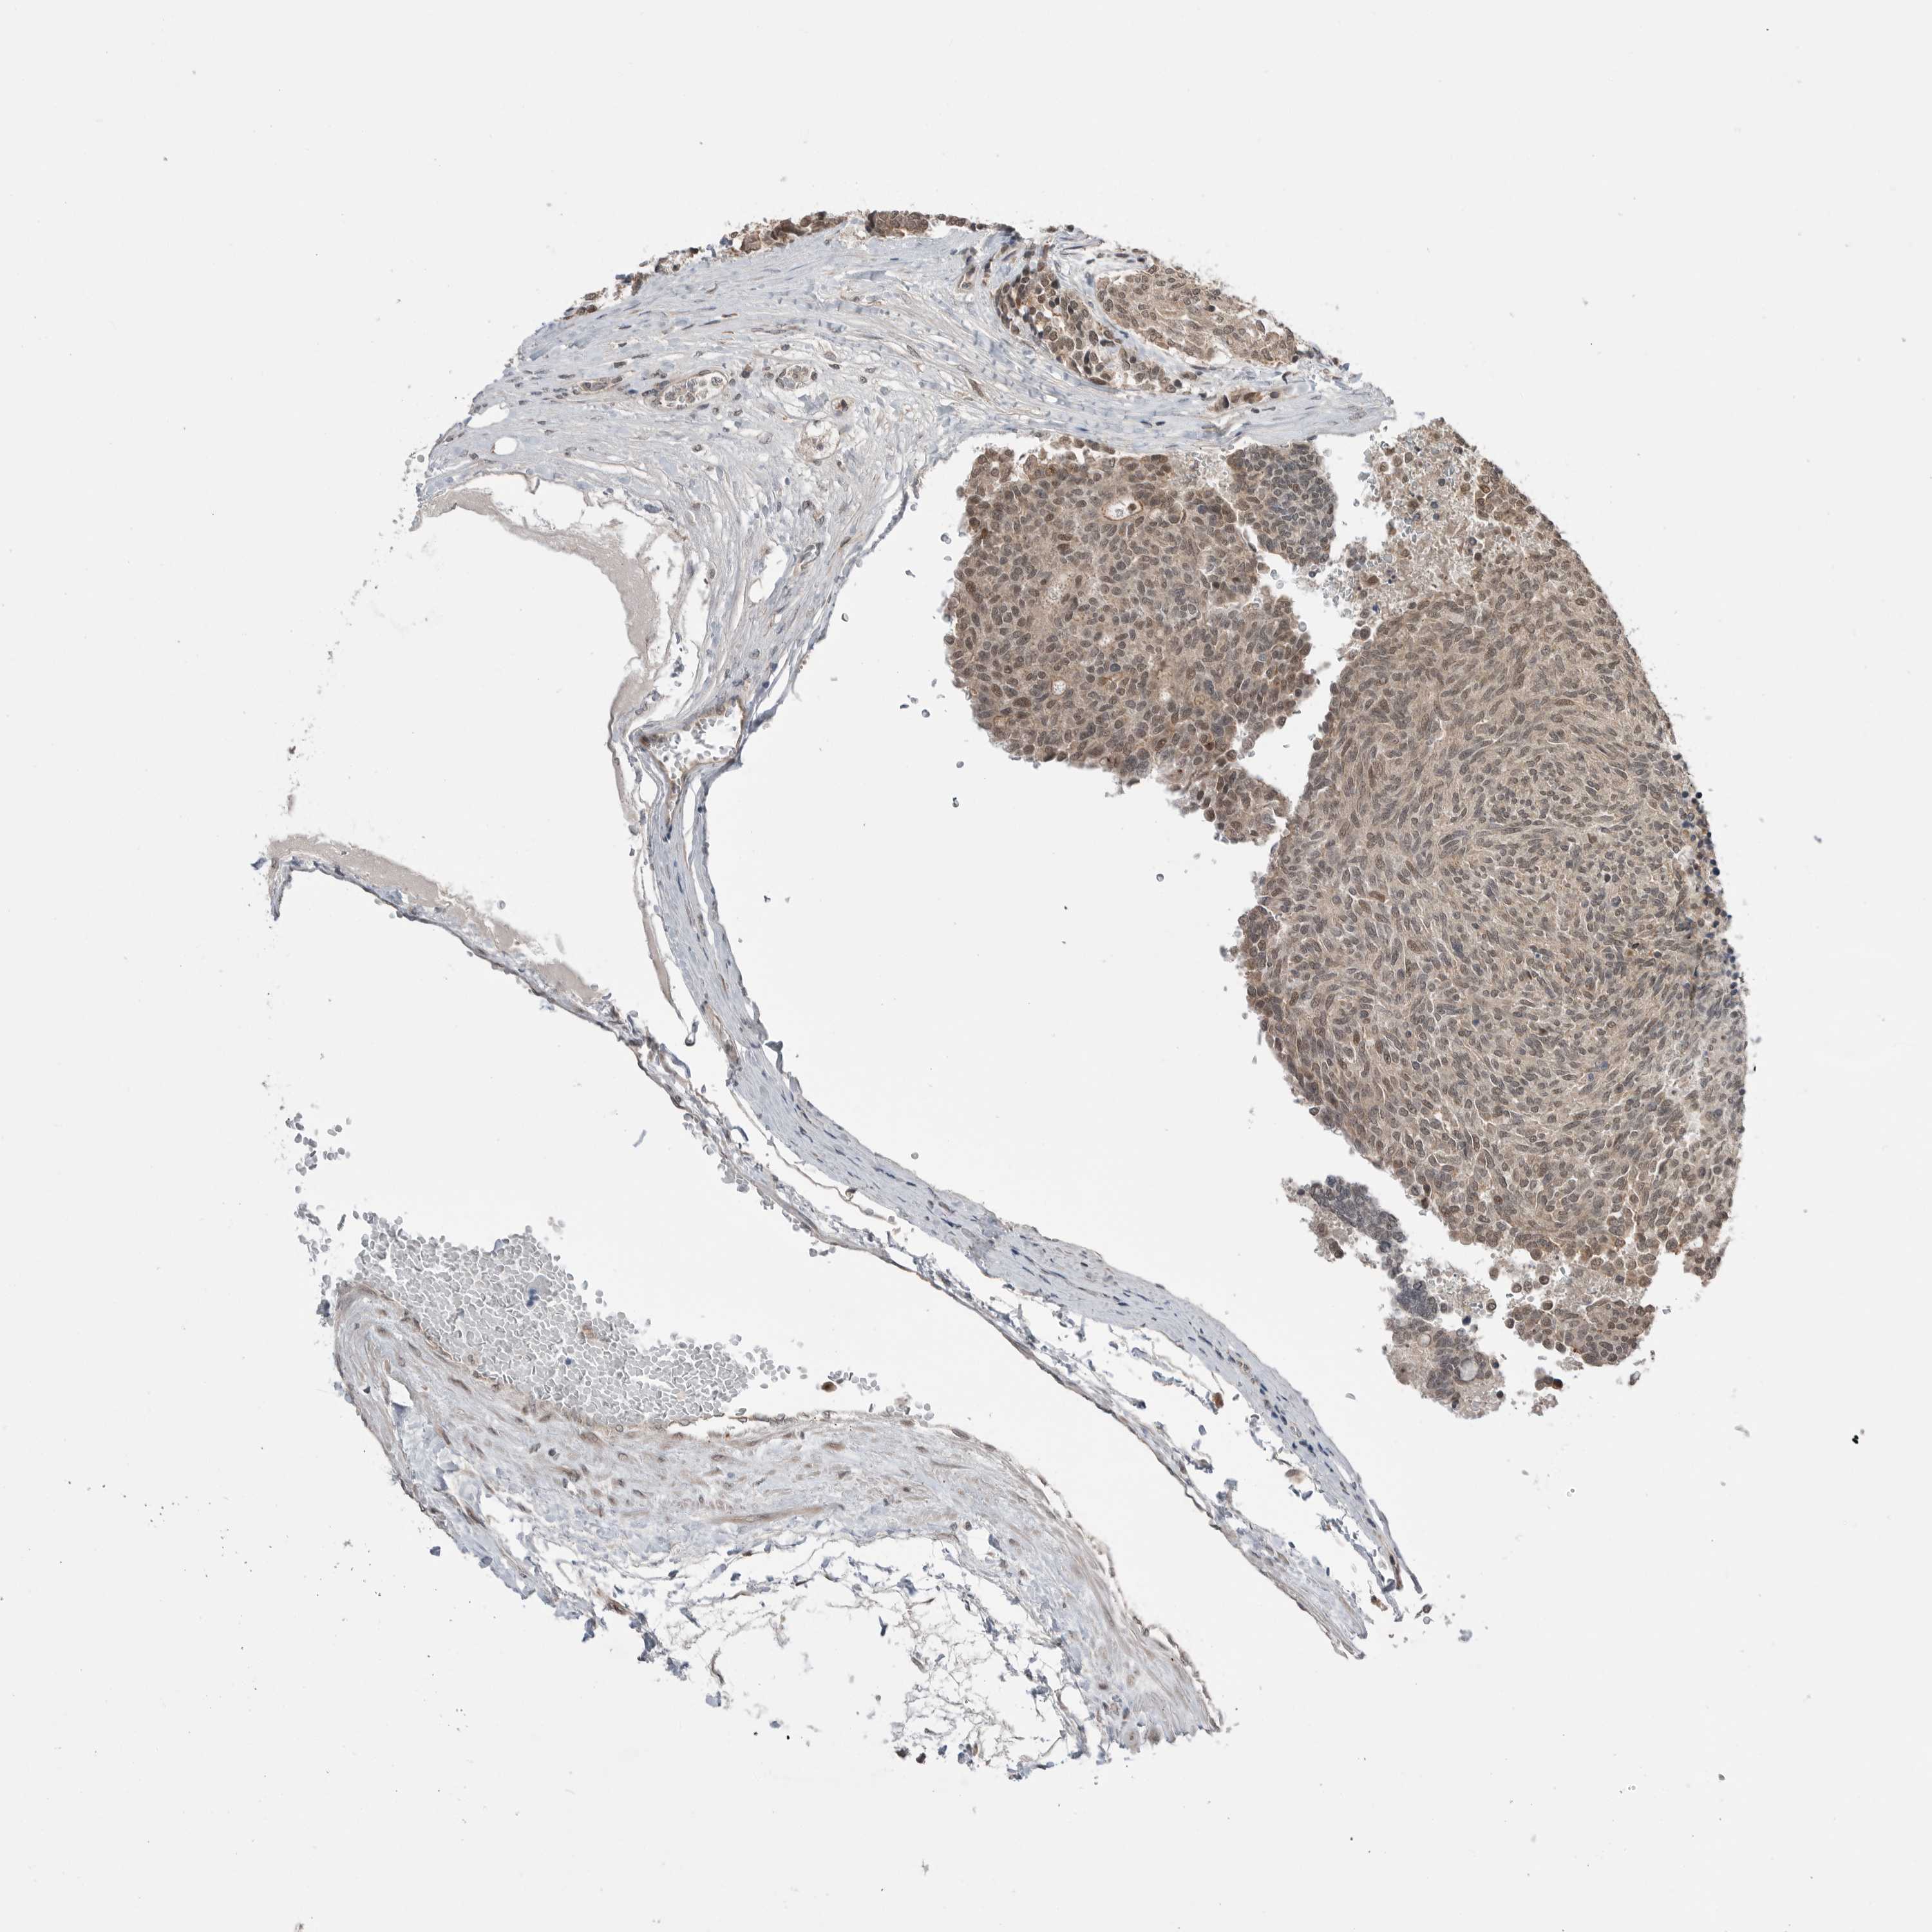

CARCINOID - Protein expressioni

A mouse-over function shows sample information and annotation data. Click on an image to view it in a full screen mode. Samples can be filtered based on level of antibody staining by selecting one or several of the following categories: high, medium, low and not detected. The assay and annotation is described here.

Antibody stainingi

Antibody staining in the annotated cell types in the current human tissue is reported as not detected, low, medium, or high, based on conventional immunohistochemistry profiling in selected tissues. This score is based on the combination of the staining intensity and fraction of stained cells.

Each image is clickable and will lead to virtual microscopy that enables deeper exploration of all samples and also displays staining intensity scores, fraction scores and subcellular localization as well as patient and tissue information for each sample.

Antibody HPA024823

Staining

High

Medium

Low

Not detected

Intensity

Strong

Moderate

Weak

Negative

Quantity

>75%

75%-25%

<25%

None

Location

Nuclear

Cytoplasmic/membranous

Cytoplasmic/membranous,nuclear

Carcinoid, malignant, NOS

Carcinoma, NOS